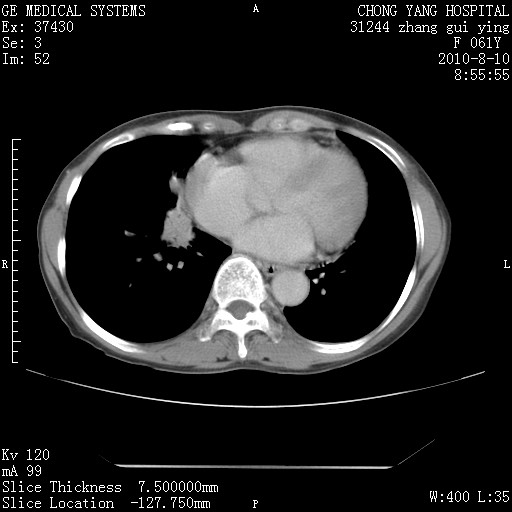

标题: CT28314:F61Y胸部增强,发热咳嗽一周入院,后面的为一周前平 [打印本页]

标题: CT28314:F61Y胸部增强,发热咳嗽一周入院,后面的为一周前平

1、支持考虑右侧中央型肺癌伴右肺中叶节段性不张及下叶支气管黏液痰栓    2、左肺上叶舌段感染。

确切的说:1:右肺下叶中心型肺癌侵及中叶支气管并中叶不张,纵膈淋巴结转移。2:左肺舌叶炎症。3:右侧胸腔少量积液

块影平扫32hu,动静脉期62-70hu.

1:右肺下叶中心型肺癌侵及中叶支气管并中叶不张,纵膈淋巴结转移。2:左肺舌叶炎症。3:右侧胸腔少量积液。支持!

右肺下叶内基底段近膈不规则肿块,考虑右肺下叶周围型肺癌可能性大。

右肺下叶中心型肺癌侵及中叶支气管并中叶不张,纵膈淋巴结转移。2:左肺舌叶炎症。3:右侧胸腔少量积液